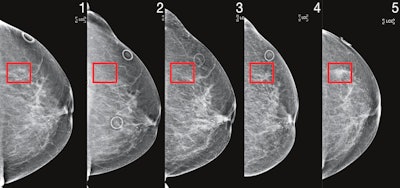

Patient identified as high risk by Mirai four years before cancer diagnosis. Image courtesy of MIT's Computer Science and Artificial Intelligence Laboratory.Importantly, Mirai also performed similarly across races, ages, and breast density categories in the MGH test set, as well as across cancer subtypes on the Karolinska dataset.